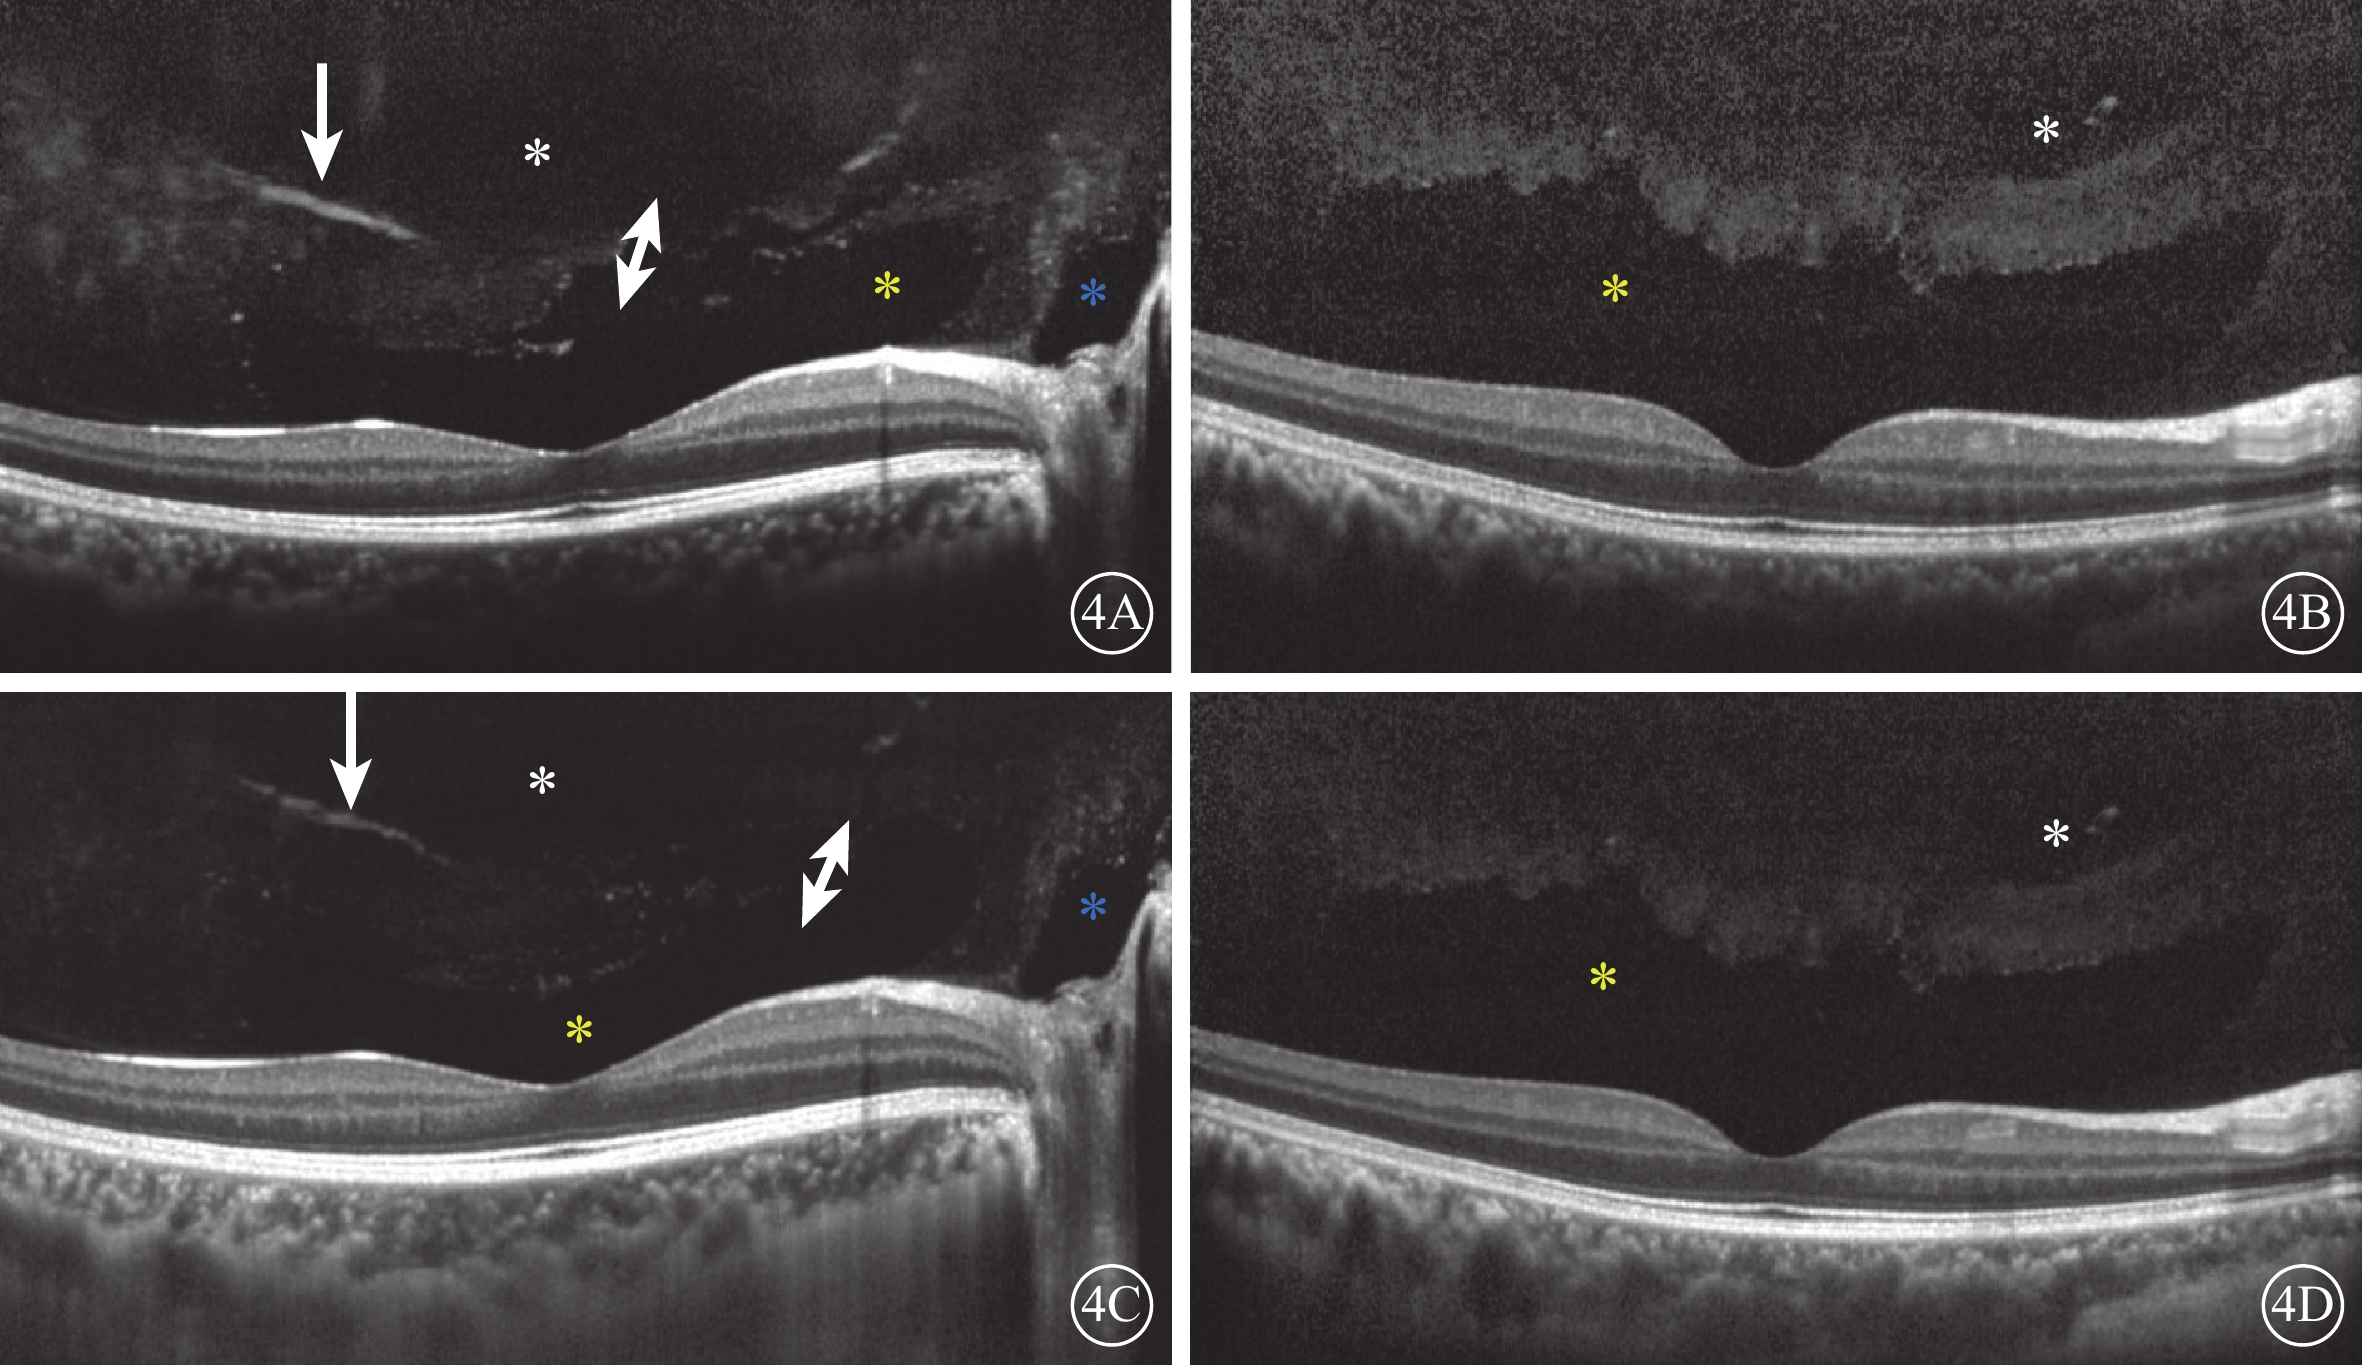

圖4

受檢眼SD-OCT像。4A、4B示后極部玻璃體掃描像;4C、4D示FDI掃描像。所有圖像均可見明顯PPVP(黃色星)和黃斑上囊(白色星)。4A、4C示部分Martegiani區(藍色星);部分玻璃體凝結(白箭),PPVP前界不光滑,與黃斑上囊出現連接通道(白色雙箭)。4C、4D示視網膜、脈絡膜成像較4A、4B清晰,但玻璃體成像清晰度較差

圖4

受檢眼SD-OCT像。4A、4B示后極部玻璃體掃描像;4C、4D示FDI掃描像。所有圖像均可見明顯PPVP(黃色星)和黃斑上囊(白色星)。4A、4C示部分Martegiani區(藍色星);部分玻璃體凝結(白箭),PPVP前界不光滑,與黃斑上囊出現連接通道(白色雙箭)。4C、4D示視網膜、脈絡膜成像較4A、4B清晰,但玻璃體成像清晰度較差

SD-OCT檢查,所有受檢眼常規檢查均未觀察到PPVP。后極部玻璃體掃描模式所采集的圖像可見PPVP結構清晰,表現為黃斑區前弱反射船形腔隙,前界為玻璃體膠原,后界為玻璃體皮質(圖2)。所有受檢眼PPVP鼻側存在一弱反射的無凝膠區域(Martegiani區),兩者之間有一隔膜將其分開。其中,單線掃描可見PPVP與Martegiani區之間存在連接通道(圖2)68只眼(66.0%);多線掃描可見所有受檢眼PPVP與Martegiani區存在連接通道,通道在某些層面出現(圖3)。PPVP前可見一個或多個黃斑上囊(圖2)16只眼(15.5%),其中黃斑上囊與PPVP之間相互連通(圖4)5只眼。PPVP伴玻璃體后脫離(PVD)(圖5)9只眼。采用FDI掃描模式進行檢查的21只眼,視網膜、脈絡膜成像清晰度較好,但玻璃體成像清晰度較差(圖4)。60只眼的PPVP平均最大水平距離為(6 895.7± 872.8)μm,平均垂直距離為(524.1±173.9)μm。

圖4

受檢眼SD-OCT像。4A、4B示后極部玻璃體掃描像;4C、4D示FDI掃描像。所有圖像均可見明顯PPVP(黃色星)和黃斑上囊(白色星)。4A、4C示部分Martegiani區(藍色星);部分玻璃體凝結(白箭),PPVP前界不光滑,與黃斑上囊出現連接通道(白色雙箭)。4C、4D示視網膜、脈絡膜成像較4A、4B清晰,但玻璃體成像清晰度較差

圖4

受檢眼SD-OCT像。4A、4B示后極部玻璃體掃描像;4C、4D示FDI掃描像。所有圖像均可見明顯PPVP(黃色星)和黃斑上囊(白色星)。4A、4C示部分Martegiani區(藍色星);部分玻璃體凝結(白箭),PPVP前界不光滑,與黃斑上囊出現連接通道(白色雙箭)。4C、4D示視網膜、脈絡膜成像較4A、4B清晰,但玻璃體成像清晰度較差